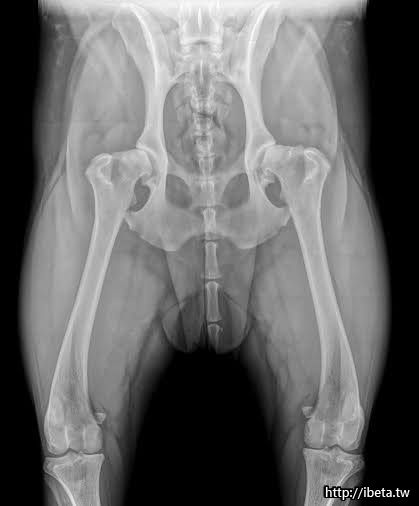

Hip Dysplasia is a common genetic disease in large breed dogs. Early detection is very important. With proper exercise, weight management and joint supplement, most of the early diagnosed patients could still maintain a good quality of life without major surgery.

髖關節發育不全在大型犬是很常見的遺傳性疾病,早期診斷非常重要,透過運動控管、體重控制及關節保養品,大部分早期發現患病的狗狗依舊可以在不需手術的情況下保有良好生活品質。